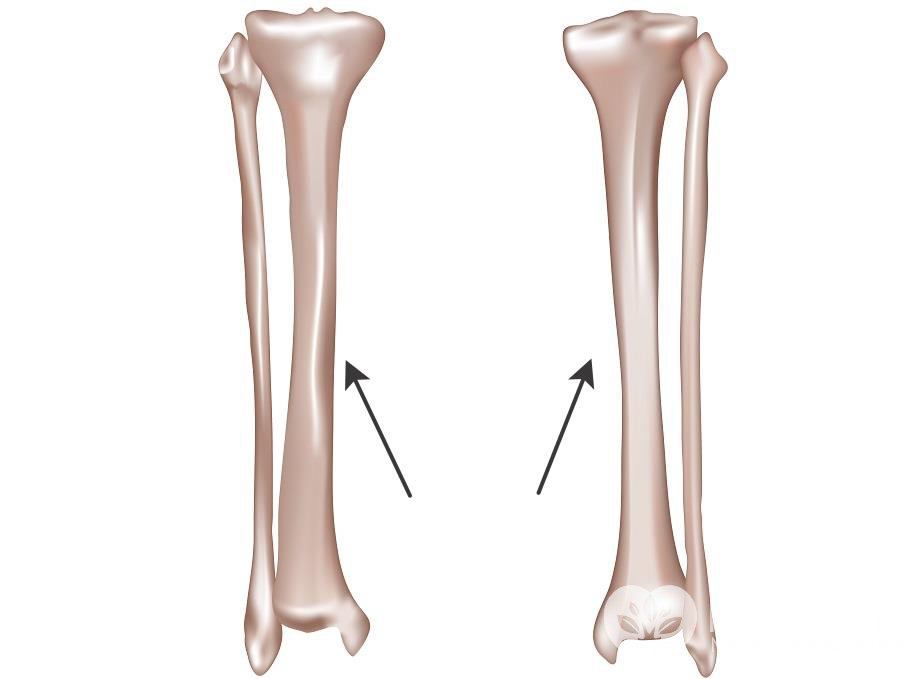

Большая берцовая кость – крупная и длинная кость голени. Состоит кость из тела и двух эпифизов – нижнего дистального и верхне...

Читать далее